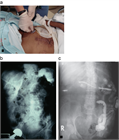

1. PEG造設後の患者には、留置後のPEG先端の位置を確認することが勧められる。